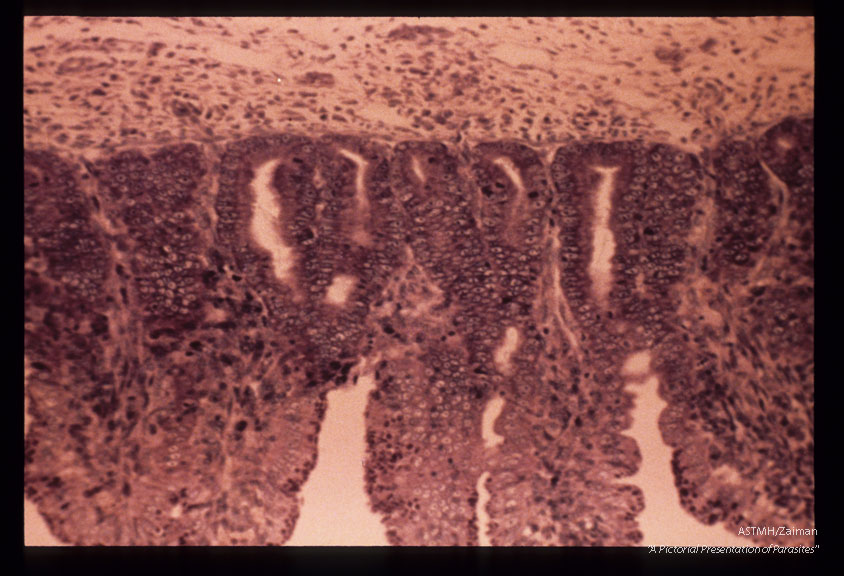

Schizonts, gametocytes in ileum of kitten. Giemsa.

Toxoplasma gondii

Description: Schizonts, gametocytes in ileum of kitten. Giemsa.